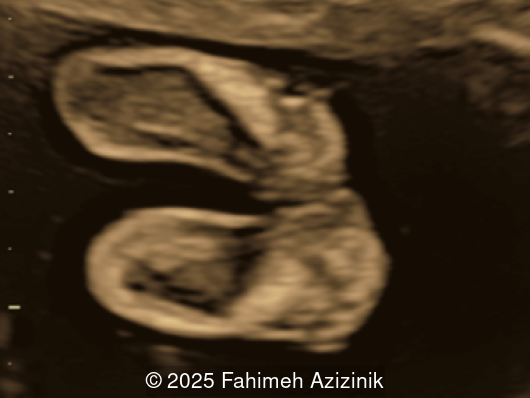

Image 3

• Complex syndactyly of the hands and feet. Complex hand brachysyndactyly with “mitten-like” appearance due to bony fusion of the fingers

Bicoronal synostosis is the characteristic cranial hallmark of Apert syndrome, detectable sonographically from 18 weeks. Its most recognizable manifestation is turribrachycephaly, defined by an elevated cephalic index (typically >85–90%) and a tall cranial vault with marked frontal bossing [19]. On prenatal ultrasound, the face in Apert syndrome shows midface hypoplasia with a depressed nasal bridge, proptosis, hypertelorism, and frontal bossing. The extremities demonstrate syndactyly of both bone and soft tissue of the hands and feet with partial-to-complete fusion often involving second, third, and fourth digits, known as “mitten hands” and “socked feet”. In severe cases, all digits are fused, with the presence of a single nail known as “synonychia” [20]. Other ultrasound findings include mild ventriculomegaly, agenesis of the corpus callosum, deficient or absent septum pellucidum, and fusion of the cervical vertebrae at the level of C5-C6 [21]. Cardiovascular (atrial and ventricular septal defect) and genitourinary anomalies (hydronephrosis, and cryptorchidia) are present in 10% of patients [22]. Increased nuchal translucency in the first trimester [23], widely open metopic suture [24], and polyhydramnios [25] have also been reported. Three-dimensional (3D) ultrasound facilitates assessment of surface abnormalities of the face and extremities, and magnetic resonance imaging (MRI) can be used to evaluate associated intracranial conditions [26].